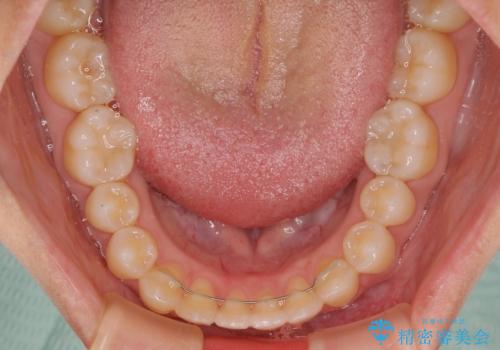

空隙歯列(すきっ歯)は、舌の突出癖をある程度改善できたとしても、後戻りにより隙間が開きやすいと言われています。

裏側から細いワイヤーで保定するとともに、睡眠時のマウスピース装着を徹底していただくことで、後戻りを最小限にとどめます。